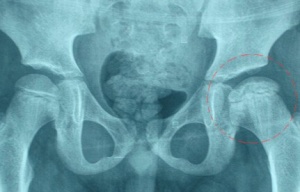

股骨頭壞死患者應該吃什么藥物來治療比較好?

相信大家都知道,近些年,股骨頭壞死發生的幾率越來越高,發生的人群也比較廣泛,小到青年,老到老年人群,都飽受股骨頭壞死的痛苦折磨。另外,藥物治療是治療該病的主要方法,那么究竟服用什么藥物才能對病情有幫助呢?

100余年研究,國內外學者一致公認:股骨頭缺血是導致壞死的主要發病機理,股骨頭壞死又稱股骨頭缺血性壞死

股骨頭壞死癥狀有以下方面,患者們尤其要注意鑒別:

疼痛:早期經常沒有任何臨床癥狀,X線片難以發現;髖部或膝部疼痛等。疼痛可為持續性或間歇性。早期疼痛多不嚴重,經過口服藥物和休息后可暫時緩解,但往往反復發作。

關節僵硬與活動受限:早期髖關節活動正常或輕微喪失,并伴有疼痛;隨著病情發展活動范圍逐漸縮小,內旋活動受限,晚期髖關節活動受限加重,甚至出現髖關節僵直。

陂行:早期為間歇性陂行,晚期患者由于股骨頭塌陷、骨關節炎及髖關節半脫位可又持續性陂行,并伴有疼痛。

股骨頭壞死分期及療效如下所示:

I期,無或隱痛;股骨頭外觀正常,軟骨、骨小梁結構稍模糊,可見輕度密度增高區或減低區,甚至可以陰性。

II期,疼痛不適,活動勞累后加重,休息后減輕、可有跛行。

III期,疼痛明顯、跛行;軟骨下骨折,出現"新月癥"或扇形骨折

IV期,全頭或大面積塌陷,股骨頭扁平,關節間隙變窄,可臨床治愈。跛行嚴重、出現功能障礙

V期,可見片狀密度增高影。可維護關節基本功能。功能明顯障礙;股骨頭變形、關節間隙明顯變窄。

VI期,功能嚴重障礙;股骨頭肥大、脫位、關節間隙完全消失、髖臼不光滑甚至硬化增生;建議行關節置換術配合藥物治療。

以上就是對股骨頭壞死癥狀的一些描述和分期,看完以上這些,相信大家對股骨頭壞死病有了一定的認識和了解。值得一提的是,通絡生骨膠囊用于股骨頭缺血性壞死癥狀有療效,有效率在90%以上,被譽為是“中西醫結合的一次重大突破”。患者們可以在咨詢醫師后進行購買。